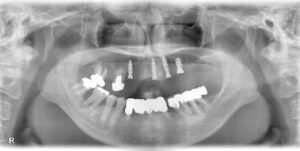

上顎インプラント前歯3本、臼歯に1本埋入

(京セラ、レリオス、ボーンレベル32の10を三本、37の6を一本埋入)

初期固定全て良し、音良し。

CT、パントモすべて良好。